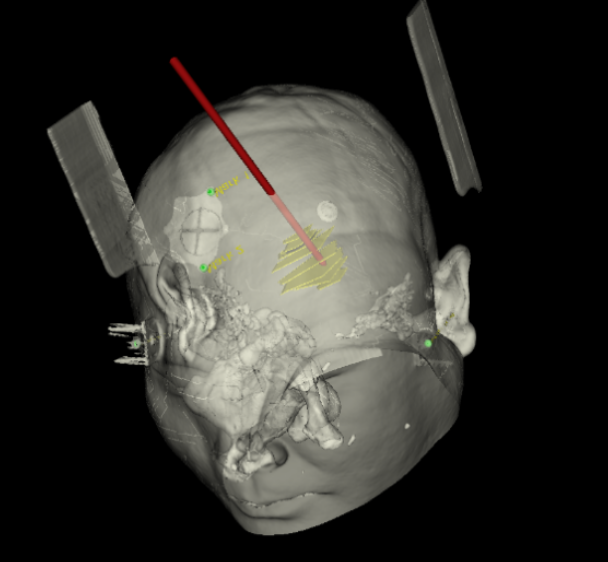

手術(shù)日當(dāng)天,醫(yī)生團(tuán)隊(duì)通過手術(shù)計(jì)劃系統(tǒng)為患者制定手術(shù)靶點(diǎn)及最安全的入顱路徑,隨后將手術(shù)規(guī)劃導(dǎo)入手術(shù)室的機(jī)器人當(dāng)中。

實(shí)際手術(shù)時(shí),機(jī)器人在幾分鐘內(nèi)就完成了空間注冊,機(jī)械臂在定位儀的引導(dǎo)下自動(dòng)定位,準(zhǔn)確鎖定靶點(diǎn)。